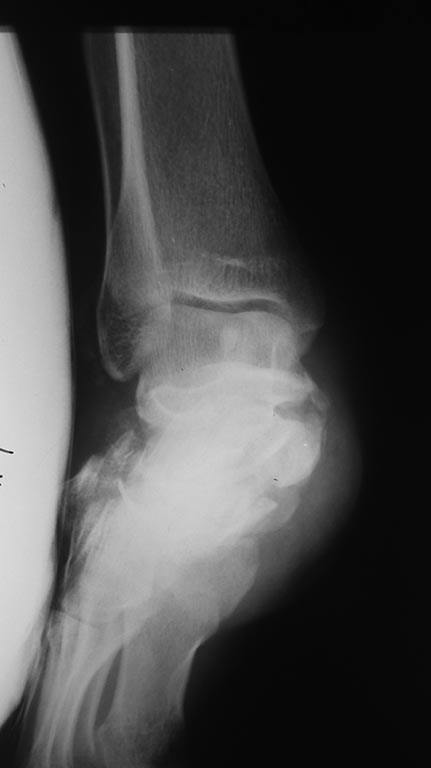

Р

2

3

Дополнительно дооперационная СКт